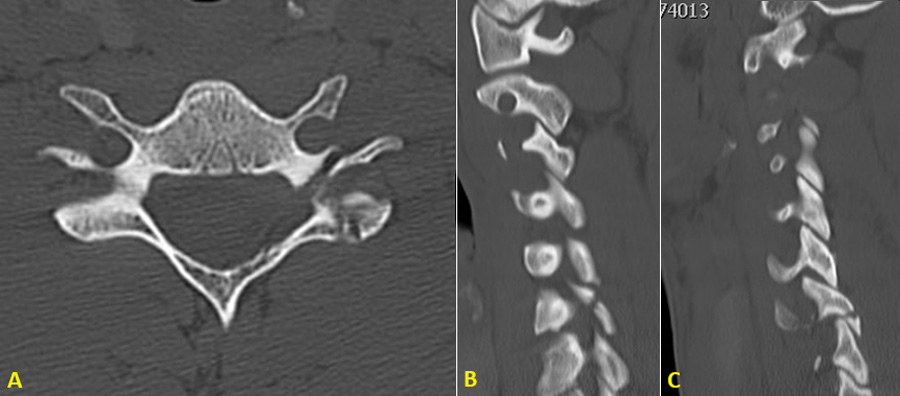

On arrival, the patient was standing, leaning rigidly against a wall, with intense neck contracture and a complete inability to mobilize the cervical spine. The neurological exam was intact (Glasgow 15). An emergency CT revealed a left-sided C6–C7 facet fracture with floating lateral mass morphology (AO-F3) without displacement. A rigid Miami J collar was placed immediately.

MRI showed significant edema of the left lamina and pedicle of C6, with increased joint effusion at the C6–C7 facet joint, anterolisthesis, a traumatic posterior disc protrusion (left-extruded) compressing the anterior dural margin, and inflammatory changes in paravertebral muscles. There was also facet fluid, subtle misalignment at C5–C6, and a high STIR signal in interspinous ligaments from C4 to C7. The spinal cord was intact, with there is no canal compromise.

Diagnosis: AO-F3 fracture of the left facet joint at C6–C7 with occult instability, confirmed by MRI.